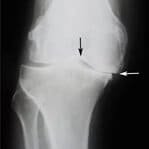

Antes

Después

1 semana